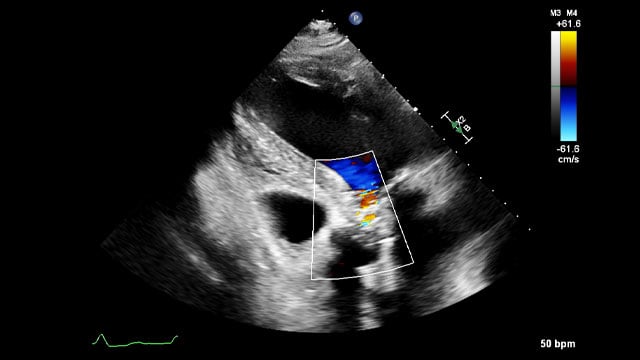

How should I treat a torrential tricuspid valve regurgitation in a young patient who remains symptomatic despite optimal medical therapy?

How should I treat a torrential TR in a young patient who remains symptomatic despite OMT?

A frail patient presents with worsening NYHA class III dyspnoea and peripheral oedema despite optimal medical therapy...